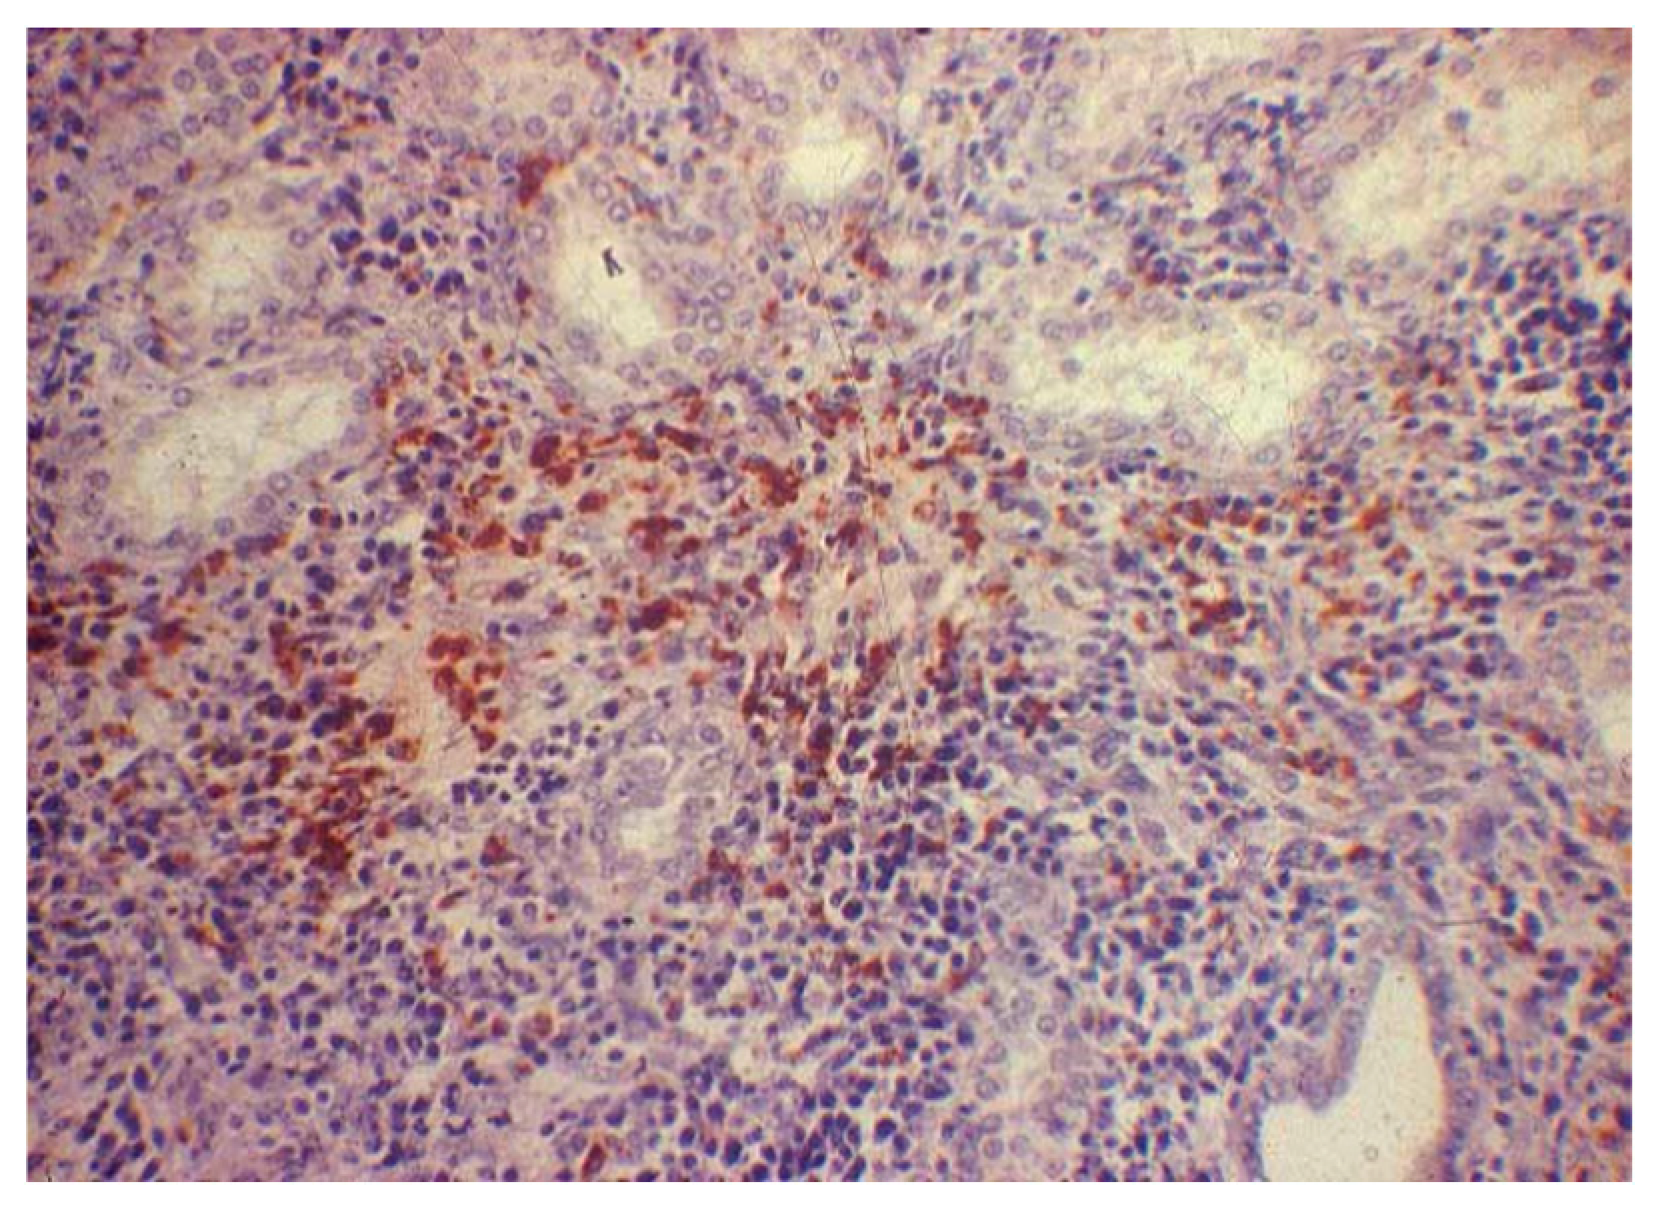

3.4. Immunohistochemical Examination